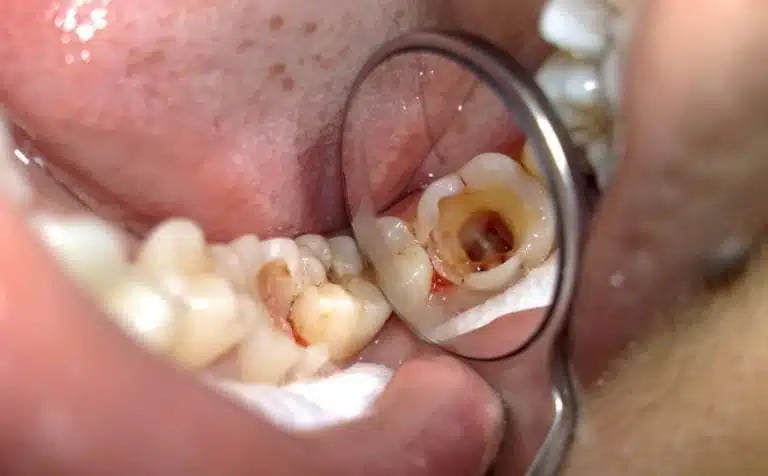

A pulpotomy treats a decayed or infected baby tooth to save it from extraction. It removes only the damaged part of the tooth’s pulp, keeping the rest healthy and your child’s smile intact.

Pulpotomy is a common pediatric dental procedure for primary (baby) teeth with decay or infection that has reached the pulp (nerve tissue). Instead of removing the entire tooth, the dentist removes only the diseased portion of the pulp and seals the remaining healthy tissue. This helps preserve the tooth until it naturally falls out, allowing proper development of permanent teeth and maintaining chewing function and alignment.